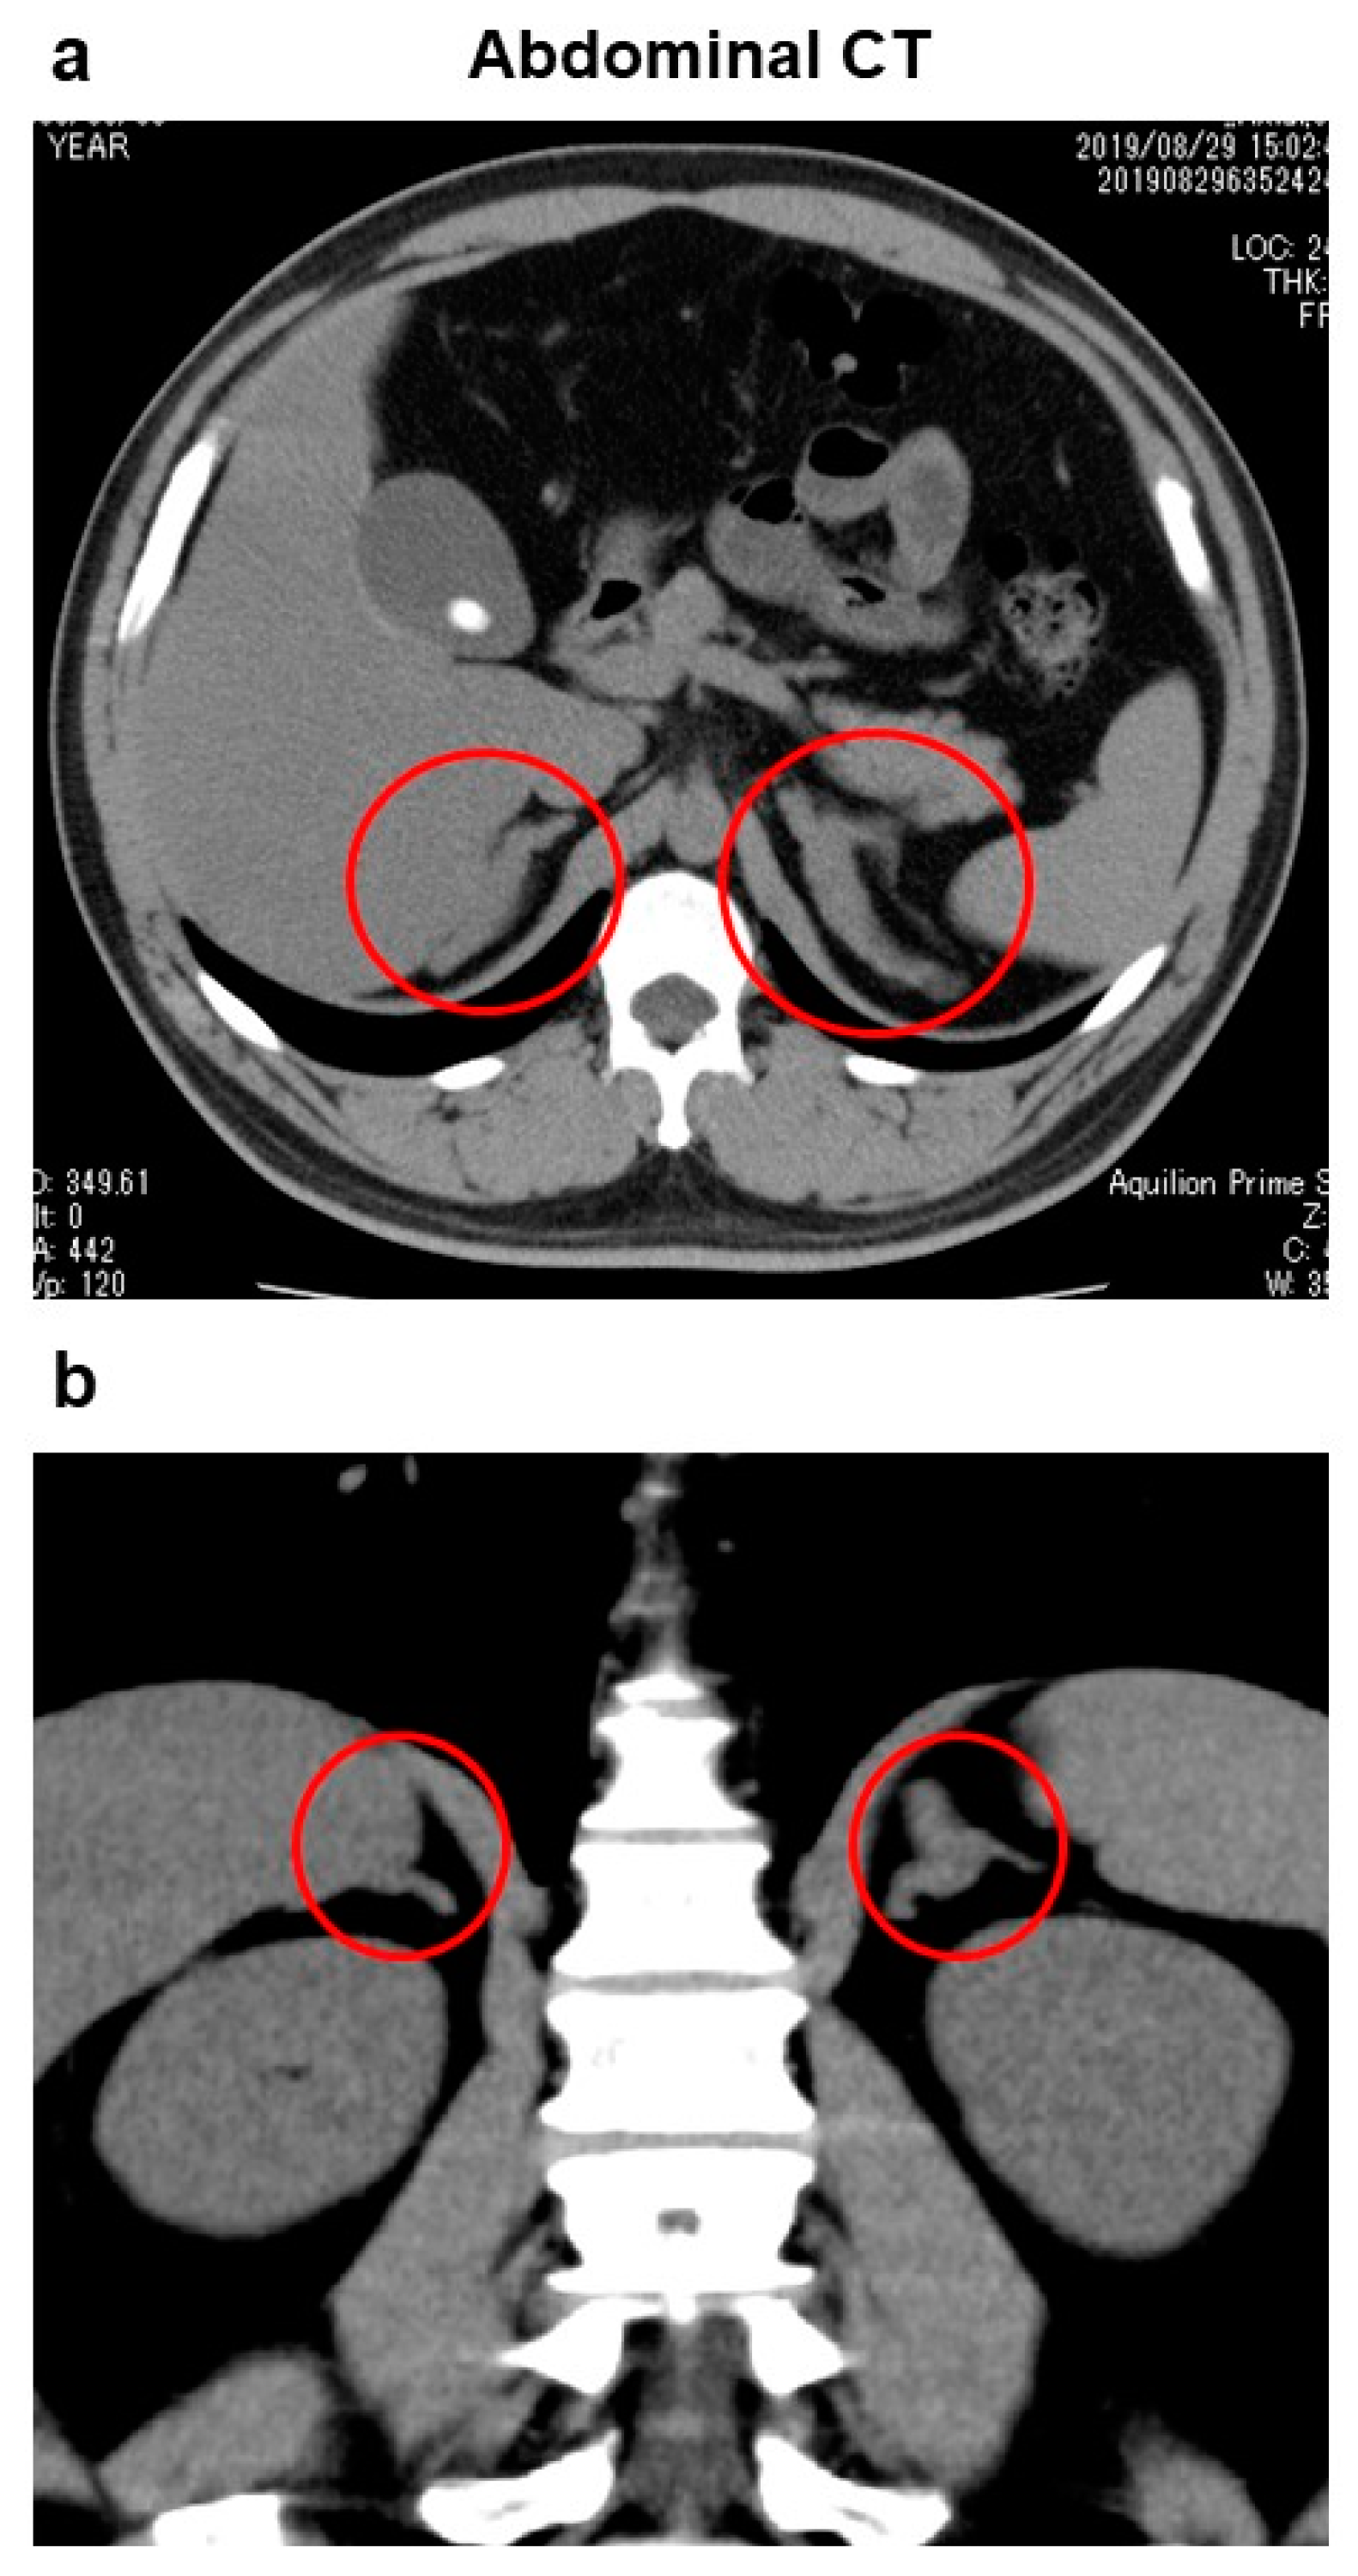

Computed tomography (CT) of the abdomen showed swelling of bilateral adrenal gland, although morphology of the adrenal glands was normal, suggesting the presence of adrenal hyperplasia (Figure 1). In addition, fatty liver, gallbladder stones and a right renal cyst were observed. There were no enlarged lymph nodes and no findings suggesting malignancy in the abdominal CT. Brain magnetic resonance imaging (MRI) showed no abnormality in the pituitary gland.

Figure 1.

Abdominal computed tomography: (a) cross-sectional image, and (b) longitudinal image. Swelling was observed in bilateral adrenal glands, although morphology was normal (circles), suggesting the presence of adrenal hyperplasia. In addition, fatty liver, gallbladder stones and a right renal cyst were observed. There were no enlarged lymph nodes and no findings suggesting malignancy.